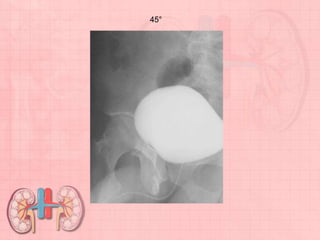

AP PROJECTION •LPO AND RPO POSITIONS • LATERAL POSITION (OPTIONAL): CYSTOGRAPHY Pathology Demonstrated Signs of cystitis, obstruction, vesicoureteral reflux, and bladder calculi are visualized. Lateral demonstrates possible fistulas between bladder and uterus or rectum. Cystography BASIC • AP (10° to 15° caudad) • Both oblique positions (45° to 60°)

AP (10° to15° caudad)

Posterior Oblique Positions: •45° to 60° body rotation. (Steep oblique positions are used to visualize posterolateral aspect of bladder, especially UV junction.) RPO (45° to 60°).